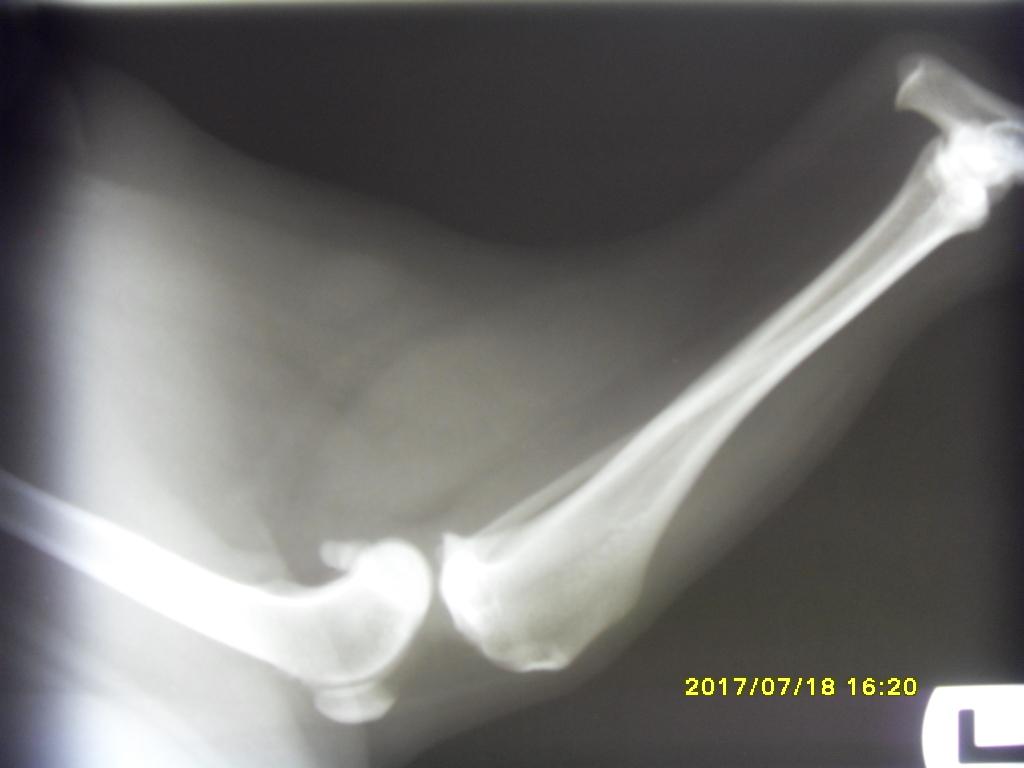

Keyq Posted July 18, 2017 Author Posted July 18, 2017 Cześc ponownie! Po dzisiejszej wizycie u weta i wykonanym teście szufladowym w premedykacji, lekarz stwierdził zerwanie więzadła krzyżowego lewej łapy. Zrobiono jej jeszcze RTG łapki i na zdjęciu było widać przesunięte kości i wysięk. Nela dostała zastrzyk z kwasem hialuronowym Synocrom Forte, Nasz psinka niestety nie może być operowana ponieważ Encorton który bierze osłabia układ odpornościowy, wystarczyło by kilka bakterii i infekcja albo inne komplikacje gotowe :/ Co do samych powiększonych węzłów chłonnych. Zrobiliśmy kolejne USG jamy brzusznej w pęcherzu moczowym dużo lepiej choć 2 "polipki" zostały jeszcze, badanie moczu wykazało ph 8, otoczka wokół nerki powiększyła się znacznie, śledziona dalej "marmurkowata". węzły szyjne zmniejszyły się o połowę (a myślałam że juz ich prawie nie ma:( ) pachwinowe znikły w całości. węzeł krezkowy nie zmniejszył się wcale :/. Powiem szczerze że spodziewałam się lepszych efektów. Encorton działa za słabo? co robić? Nie będę mogła zoperować psa póki Encorton nie wyleczy węzłów, wet jednak zalecił kolejna biopsje więc na następnej wizycie pobierze próbki z kilku węzłów, kolejne USG jamy brzusznej i krew. Lekarz kazał się jednak przygotować na najgorsze, Nela najprawdopodobniej ma chłoniaka. My z mężem już pogodziliśmy się z faktem że będziemy musieli się z nią pożegnać. :( poniżej wrzucam rtg zdrowej prawej i chorej lewej łapki Quote